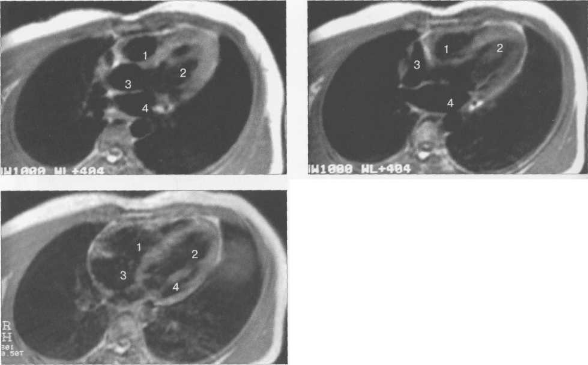

КТ АНАТОМИЯ СЕРДЦА

КТ-исследование позволяет получать поперечные (аксиальные) сечения сердца. Стандартная пошаговая КТ и даже спиральная КТ не получили распространения для исследования морфологии и функции сердца. Более тщательный анализ внутрисердечных структур возможен с помощью многослойной спиральной КТ (МСКТ) в условиях внутривенного контрастирования. КТ-изображения сердца и сосудов на различных уровнях представлены на рис. 9.34.

Рис. 9.34. КТ сердца и сосудов.

1 — правый желудочек; 2 — левый желудочек; 3 — правое предсердие; 4 — левое предсердие; 5 — межжелудочковая перегородка; 6 — межпредсердная перегородка; 7 — верхняя полая вена; 8 — восходящая часть аорты; 9 — нисходящая часть аорты; 10 — легочный ствол; 11 — правая легочная артерия; 12 — диафрагма; 13 — легочные вены.

МСКТ в условиях внутривенного болюсного контрастирования позволяет визуализировать коронарные артерии (МСКТ-коронарография). Анализ состояния коронарных артерий выполняется сначала на аксиальных срезах (рис. 9.35). В постпроцессинговой обработке изображений используются различные виды реконструкций: многоплоскостные реформации (MPR), проекция максимальной интенсивности (MIP), трехмерные (VRT) (рис. 9.36).